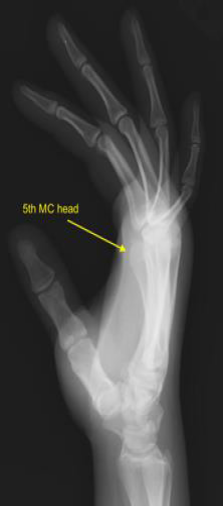

مفاصل قاعدة الأصابع (CMC الثاني إلى الخامس)

- مفصل CMC الخامس: يتصل حصريًا بالعظم الكلابي. وهو الأكثر حركة بين مفاصل CMC الأصابع، مما يسمح بثني ودوران كبيرين. هذه الحركة ضرورية لقدرة الإصبع الخنصر على الانحناء والتكيف مع الأشياء أثناء الإمساك بقوة.

- الميكانيكا الحيوية: تنقل الصلابة الجوهرية لمفاصل CMC الثاني والثالث القوى المحورية بكفاءة من الساعد عبر الرسغ إلى اليد. وعلى العكس، تسمح الحركة الأكبر لمفاصل CMC الرابع والخامس بالتشكيل الديناميكي لقوس راحة اليد، وهو أمر بالغ الأهمية للإمساك التكيفي والتلاعب بالأشياء. يمكن أن يؤدي اضطراب هذه المفاصل، وخاصة تلك الأكثر حركة في الجانب الزندي، إلى إضعاف كبير لقدرة اليد على تشكيل قوس وظيفي وتقليل قوة الإمساك.